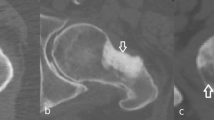

Image processing was conducted using Mimics Research (V21.0, Materialise NV, Leuven, Belgium). Mimics Research is well-established for evaluationing anatomical 3D models and was approved by the Federal Drug Administration (FDA) for medical applications [39], ensuring optimal comparability with previous studies and useability in future research. The segmentation of all CT image series employed a single automatic threshold (SAT) with a minimum set at 226 Hounsfield units (HU) and the radius models were isolated using the “region grow” tool. Manual removal of connecting voxels to the carpal bone was performed (using the multi-slice edit tool). Subsequently, the models were filled using the “smart fill” tool, considering that only the outer contour could be compared to the surface scans. Following this, 3D parts (CAD models) were generated (setting: “optimal”) and post-processed with the “wrap” (one pixel “smallest detail”, half a pixel as “gap closing distance”) and “smooth” tools (two iterations, smooth factor 0.3, according to [30]). Additionally, scan series from the SOMATOM Force utilizing the optimized protocol were segmented with a multi-manual threshold (MMT), as outlined in Fig. 2. In essence, specific thresholds for the cortex of the diaphysis and the epiphysis were determined using a line intensity profile. Four regions are defined in a single plane: soft tissue, bone cortex, bone cortex, and soft tissue and their HU values were evaluated. The lower segmentation threshold was set at a 50% difference between the assessed HU values, as described previously [40]. The upper segmentation value was not limited. Overlapping regions of the mask for the epiphysis were deleted using the “split” tool and then merged to obtain a single segmented mask. 3D part generation and post-processing were conducted analogouslyto the described SAT algorithm.

Segmentation with the multi manual threshold. A profile line is drawn in the center of the diaphysis and the epiphysis. Four regions are marked: 1 & 4: soft tissue, 2 & 3: cortical bone. Thresholding is performed as the 50% difference between those regions. The epi- and diaphysis are separated with region grow. The epiphysis is split to remove bone regions already present in the diaphysis and finally merged into one bone model